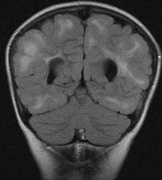

Mental retardation and seizures in TSC are often associated with benign CNS astrocytic hamartomas.131 On imaging, the cerebral lesions show three patterns:132

1. Superficial cortical sclerosis (parenchymal hamartoma) which distort the gyri. Microscopy shows large atypical fibrillary type astrocytes with few associated neurons and areas of calcification.133 The numerous abnormal glial processes and fibers make the tissue abnormally firm or “sclerotic” on palpation (Fig. 13).132

2. Subependymal nodules (SEN) are typically found along the lateral borders of the ventricles and parehncymal brain lesion (“cortical tubers”) (Figs. 14 and 15). Calcification in the first year of life is rare.132

3. White matter abnormalities are a characteristic “ventriculofugal” pattern corresponding to the embryological migratory paths of neurons and glia. These lesions may represent aberrant neuronal migration, a possible reflection of haploinsufficiency for the TSC gene.116,132,134

On MRI imaging, the subependymal nodules and parenchymal brain lesions of infants (age ≤3 months) and adults show different signal characteristics. Infant CNS tubers are hyperintense on T1-weighted images and hypointense on T2-weighted images, which is the opposite of the pattern seen in adults.134 Malignant transformation of SEN occurs in about 10% to 15% of patients and the resultant subependymal giant cell astrocytoma accounts for 25% of premature deaths in TSC.135,136

Fig. 14. Tuberous Sclerosis Complex: Sub-Ependymal nodules. These are typically found along the lateral borders of the ventricles.132

Fig. 15. Tuberous Sclerosis Complex. (a) Patient 1: Axial CT scans demonstrating typical calcification of subependymal nodules in a 13-year-old girl with a history of seizures. (b and c) Patient 2. (b) Axial T2-weighted images demonstrate calcified subependymal nodules (arrowheads) and cortical tubers typical of tuberous sclerosis. (c) Widespread cortical tubers are seen on a coronal FLAIR sequence as thickening of the cortex and high signal of the subcortical white matter.